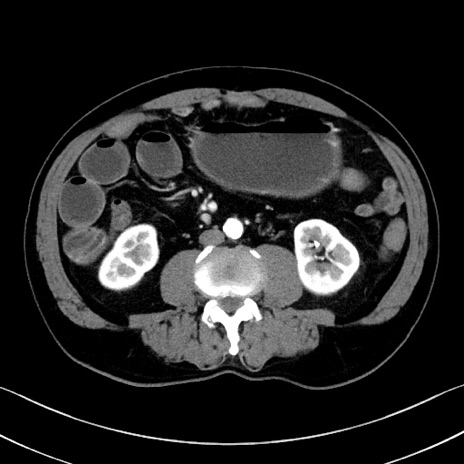

症例35(横断像)

【症例】70歳代 男性

【主訴】腹部膨満、嘔吐

【現病歴】昨日より腹部膨満感出現。本日増悪し、仙痛出現。嘔吐あり、受診。

【既往歴】糖尿病、胆摘後

【身体所見】BP 149/80mmHg、HR 74/min、BT 35.9℃、腹部:膨満、軟、圧痛なし。腸雑音減弱あり。上腹部正中切開瘢痕あり。

【データ】WBC 13500、CRP 1.72